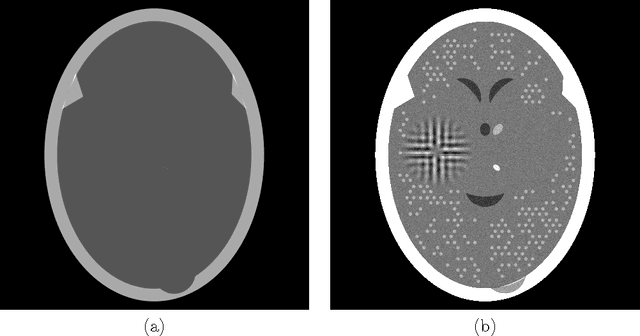

Abstract:To reduce the x-ray dose in computerized tomography (CT), many constrained optimization approaches have been proposed aiming at minimizing a regularizing function that measures lack of consistency with some prior knowledge about the object that is being imaged, subject to a (predetermined) level of consistency with the detected attenuation of x-rays. Proponents of the shearlet transform in the regularizing function claim that the reconstructions so obtained are better than those produced using TV for texture preservation (but may be worse for noise reduction). In this paper we report results related to this claim. In our reported experiments using simulated CT data collection of the head, reconstructions whose shearlet transform has a small $\ell_1$-norm are not more efficacious than reconstructions that have a small TV value. Our experiments for making such comparisons use the recently-developed superiorization methodology for both regularizing functions. Superiorization is an automated procedure for turning an iterative algorithm for producing images that satisfy a primary criterion (such as consistency with the observed measurements) into its superiorized version that will produce results that, according to the primary criterion are as good as those produced by the original algorithm, but in addition are superior to them according to a secondary (regularizing) criterion. The method presented for superiorization involving the $\ell_1$-norm of the shearlet transform is novel and is quite general: It can be used for any regularizing function that is defined as the $\ell_1$-norm of a transform specified by the application of a matrix. Because in the previous literature the split Bregman algorithm is used for similar purposes, a section is included comparing the results of the superiorization algorithm with the split Bregman algorithm.